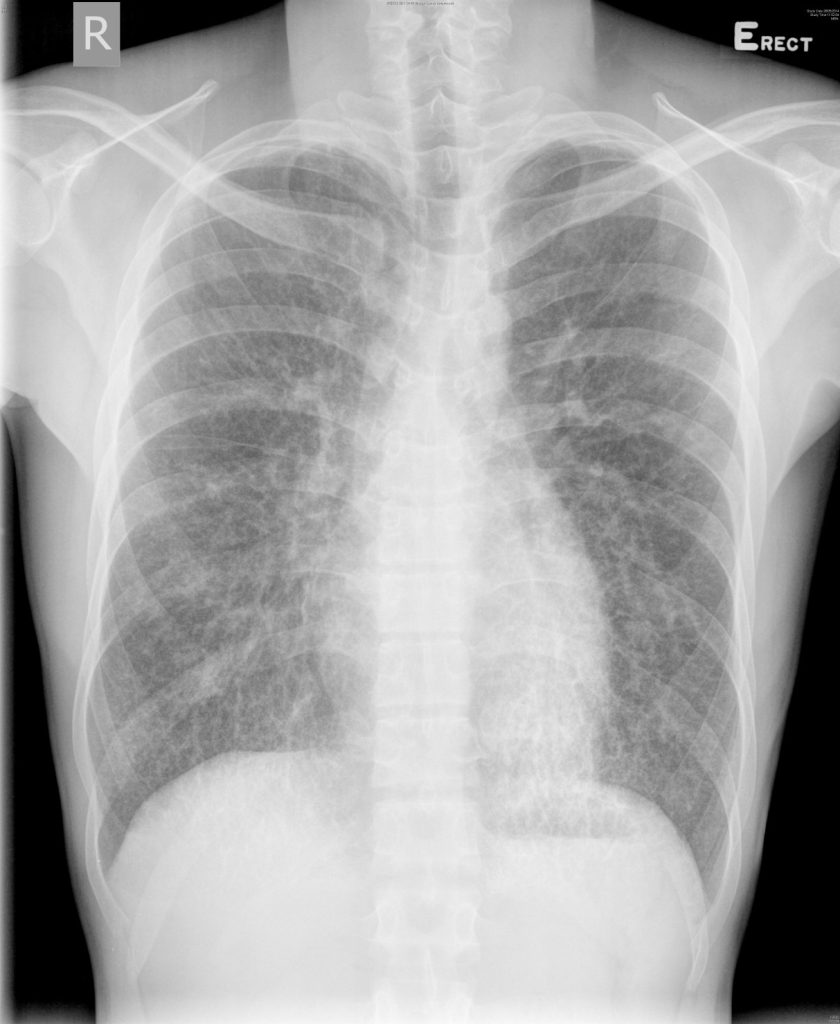

A 25 year old Chinese man, nonsmoker and nondrinker, presented to the private urologist for bloody semen. Chest X-ray (Figure 4) was performed and showed bilateral nodular shadows. He was referred to chest clinic then to our unit for further management.

Figure 4 Chest X-ray on admission

Our patient had no cough, dyspnea or hemoptysis and he had no constitutional symptoms. Physical examination was unremarkable. Blood tests included complete blood count, liver and renal function test, calcium and phosphate were normal. His sputum and early morning urine for AFB smears were negative and sputum for cytology was also negative. Several investigations were done in private and they included KUB which did not reveal any renal stones, ultrasonography of the prostate and bladder showed multiple calcifications along the ejaculatory ducts in the seminal vesicles. HRCT was performed (Figure 5) and it revealed nonspecific reticulonodular shadow in both lungs with subpleural predominance. Pulmonary function test was performed and showed normal spirometry and lung volume with mild diffusion defect. The FEV1 was 3.31L(86% predicted), FVC was 3.73L(83% predicted) with FEV1/FVC ratio of 0.89, TLC was 84% predicted and DLCO was 68% predicted.